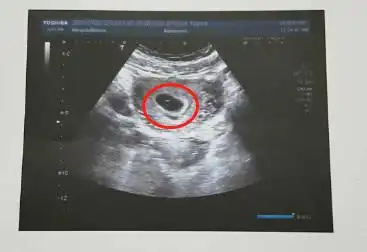

报告上写着是一个孕囊,但是图上确有两个小东西,同事朋友都说不像是

当时40天的时候去检查只有孕囊,无胎心胎芽,把我们担心的,过了3周,去

我怀孕两个月了,我就想知道这个东西是孕囊吗?